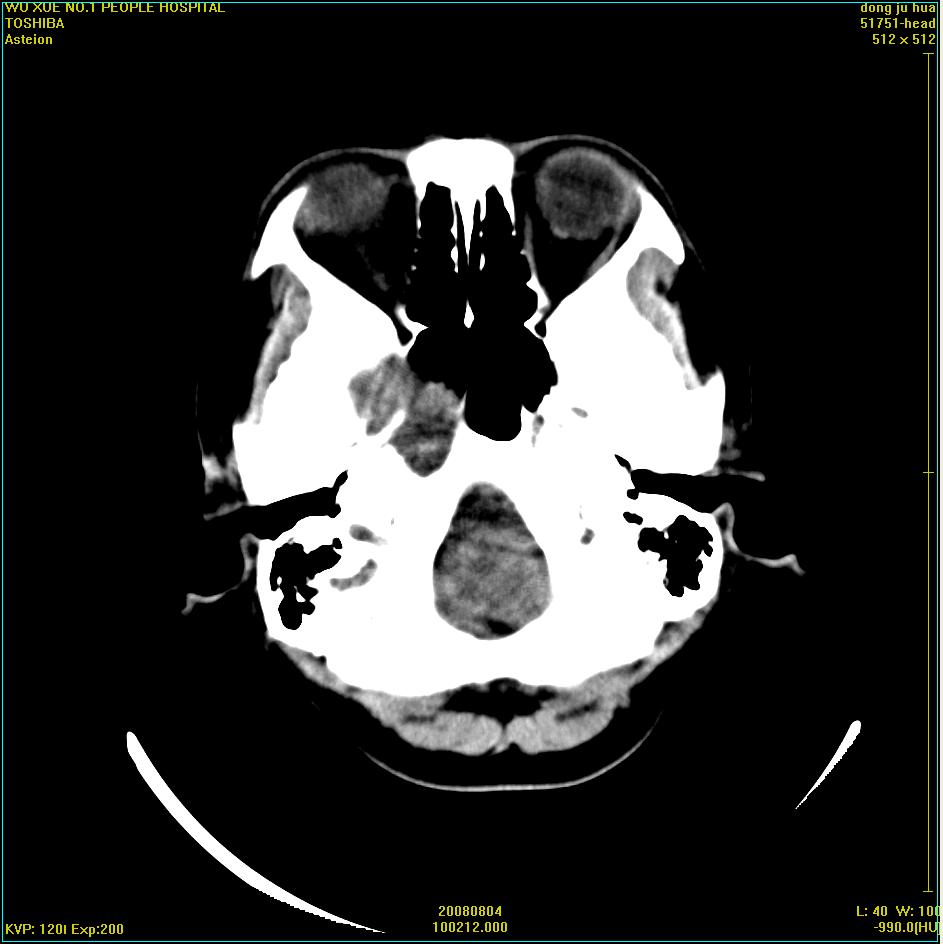

标题: CT15022:女,45岁。右侧桥小脑脚区三叉神经鞘膜瘤,已做手 [打印本页]

标题: CT15022:女,45岁。右侧桥小脑脚区三叉神经鞘膜瘤,已做手

患者,女,45岁。四年前在我院做ct诊断为右侧桥小脑脚区三叉神经鞘膜瘤,已做手术。今复杳。请大家看看

三叉神经鞘膜瘤术后

考虑三叉神经鞘膜瘤术后复发并瘤体内出血。

三叉神经鞘膜瘤术后复发并瘤体内出血